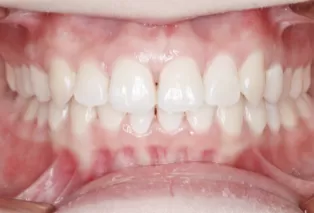

Intraoral photos